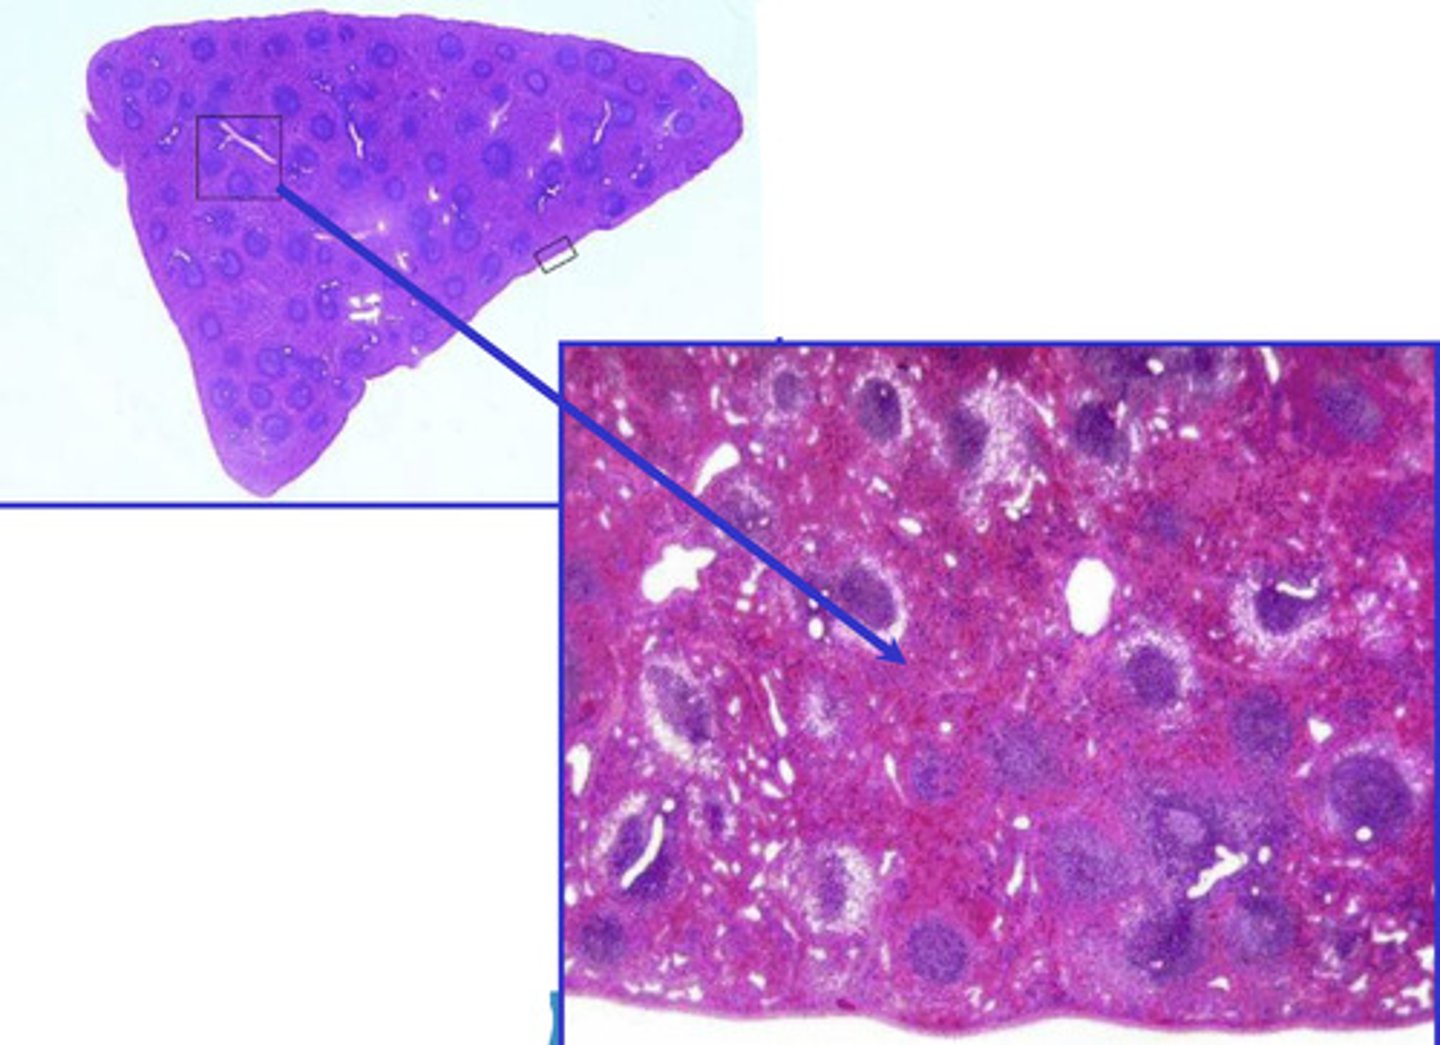

red bone marrow

what is this?

yellow bone marrow

what is this?

spleen

what is this?

spleen

what is this?